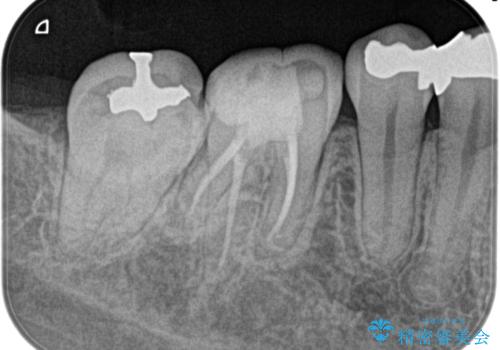

奥歯が痛い。精密根管治療〜オールセラミッククラウン

奥歯の根管治療~オールセラミッククラウン